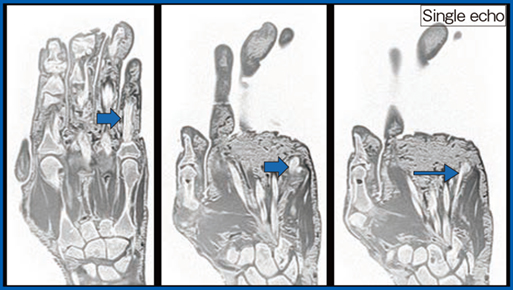

腰椎分離症疑いや指屈筋腱断裂疑い評価などのMRIが苦手とする検査依頼に対しては,CT like imageの追加が有用である。CT like imageを作成しMPRで評価することで,骨折によって完成した腰椎分離症や分離部の骨肥厚を安定して評価可能である。また,指屈筋腱断裂の評価に当たり,手はきわめて微細な構造で構成されており,手指の変形も強いため,2D画像だけで断裂部位を評価するのは困難である。CT like image(図5)では,MP関節レベルで腱(→)が急激に細くなっていることが視認でき,断裂していることが推定できる。

図5 CT like imageによる指屈筋腱断裂の評価